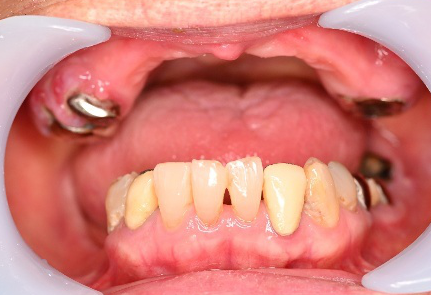

Before

After

【義歯を装着したところ】

【義歯を外したところ】